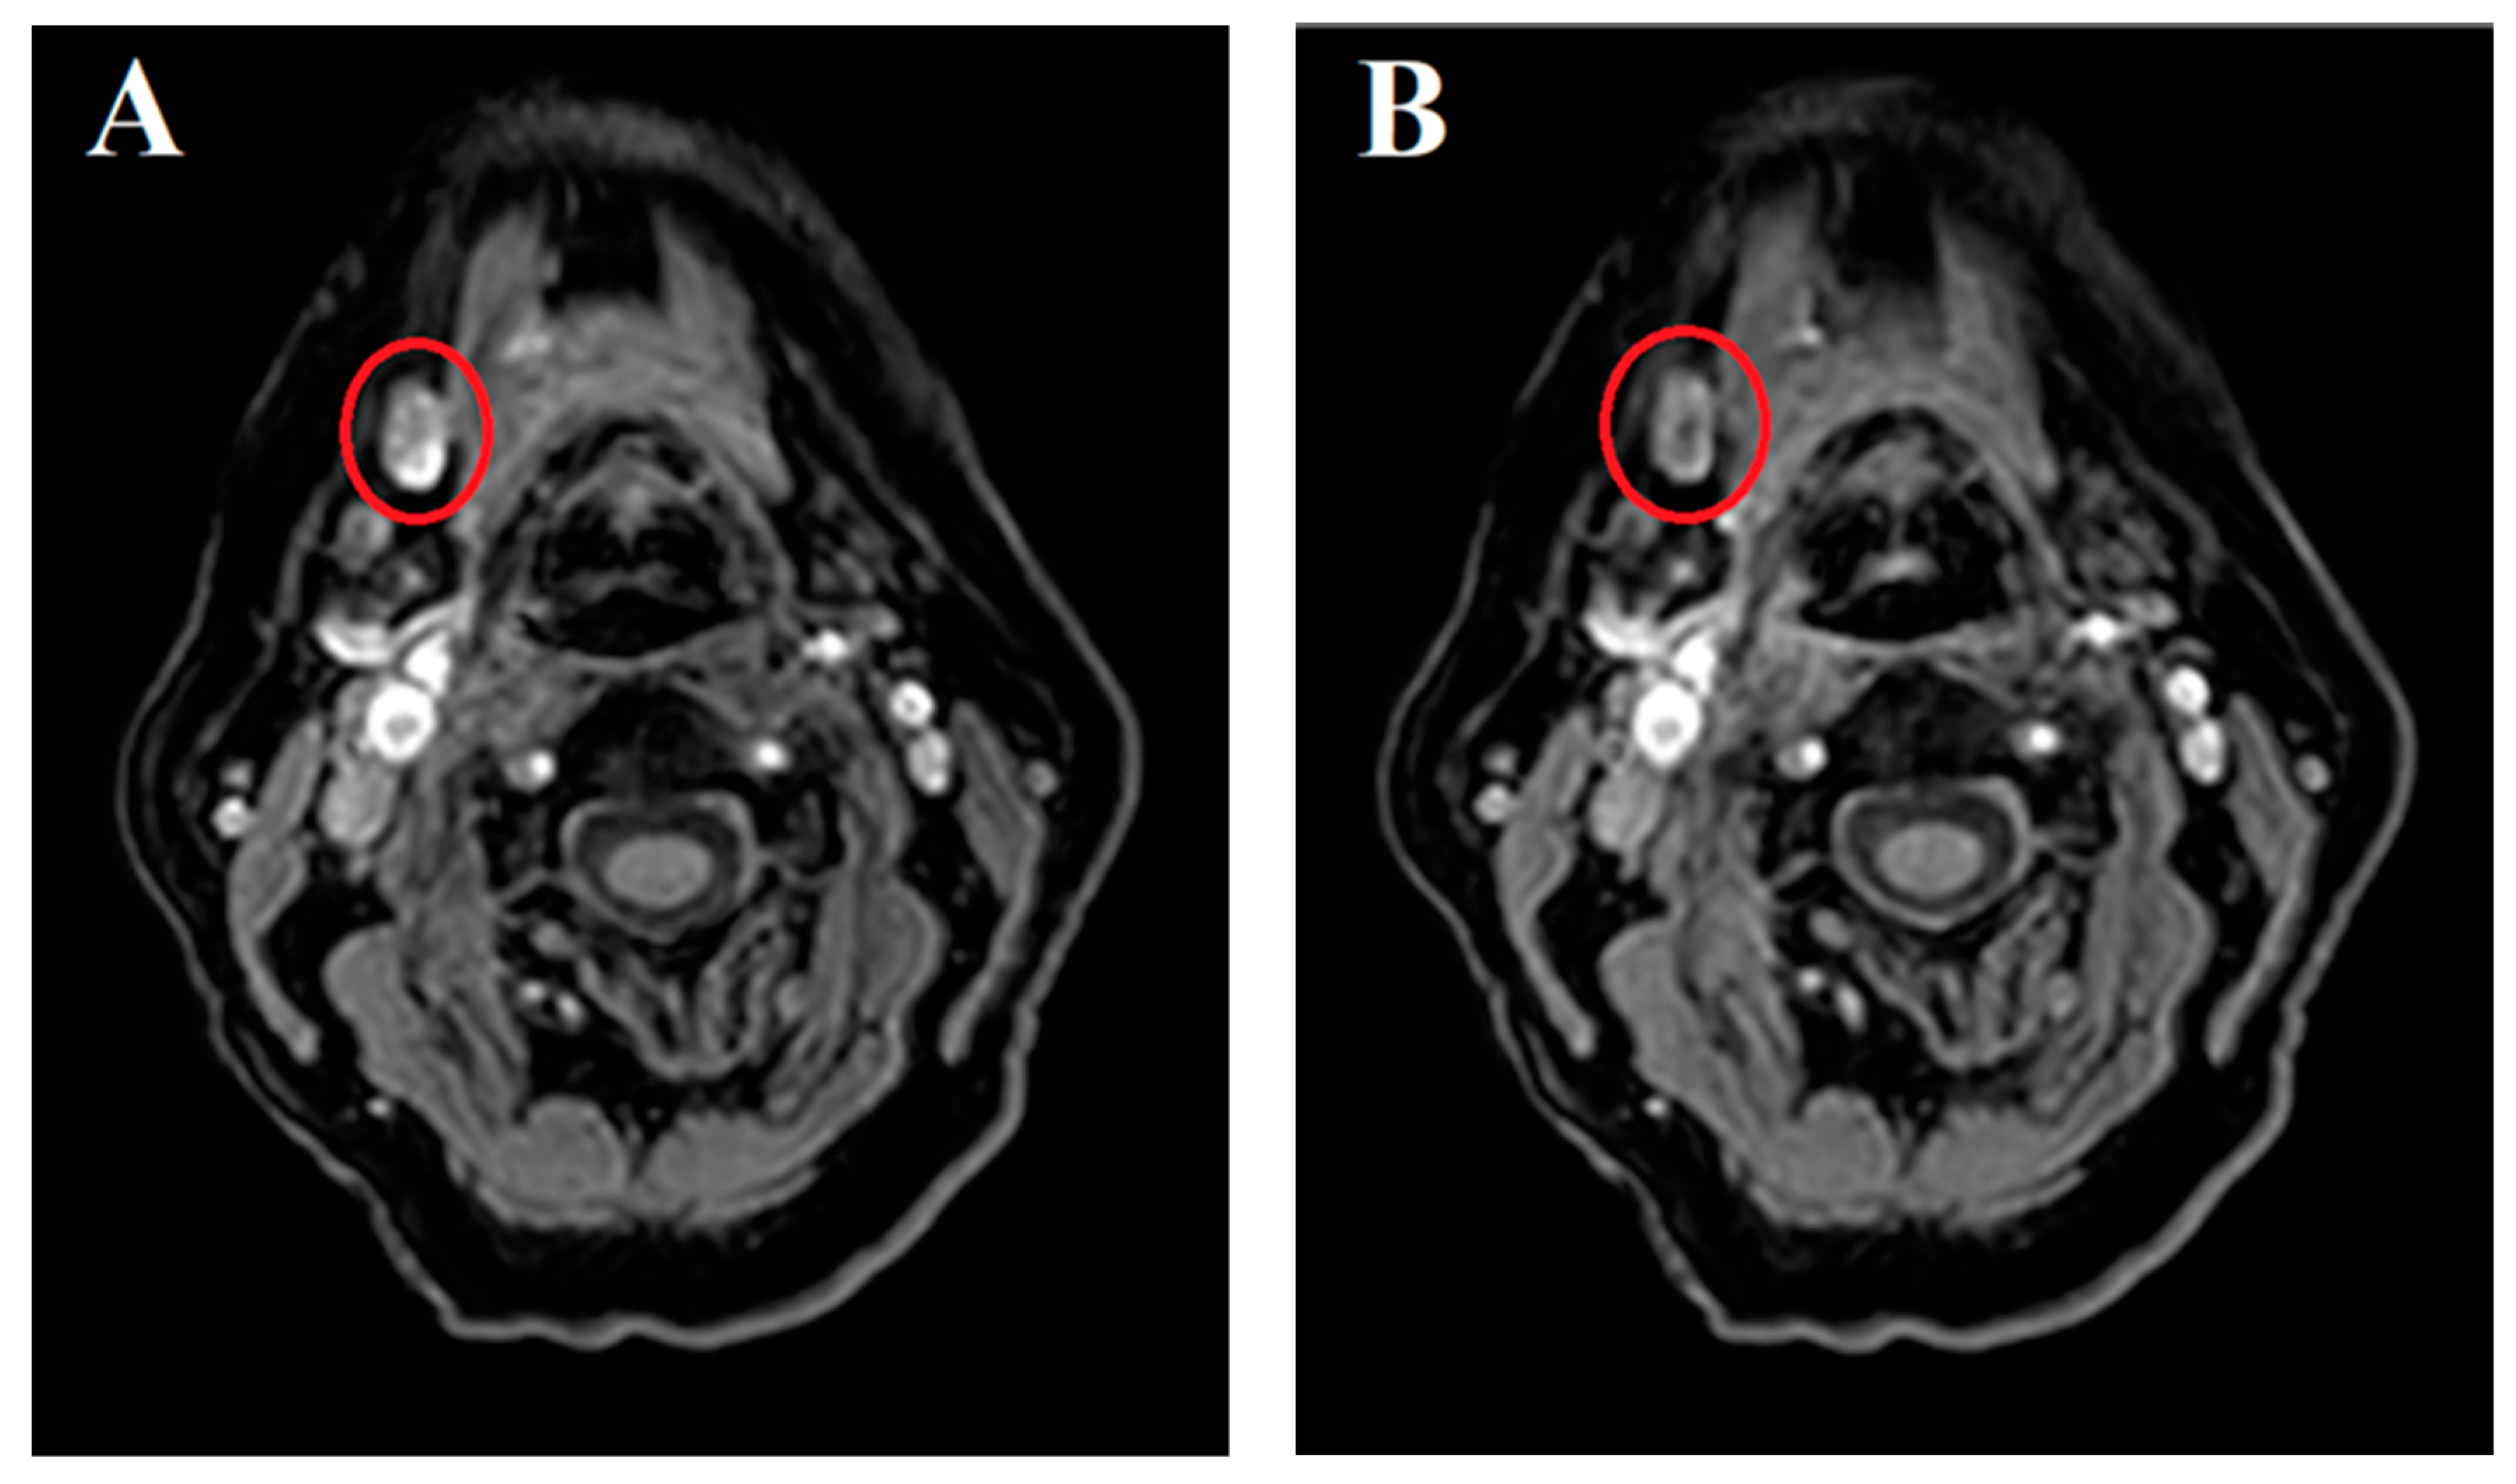

Sentinel Lymph Node Identification on MR Lymphography